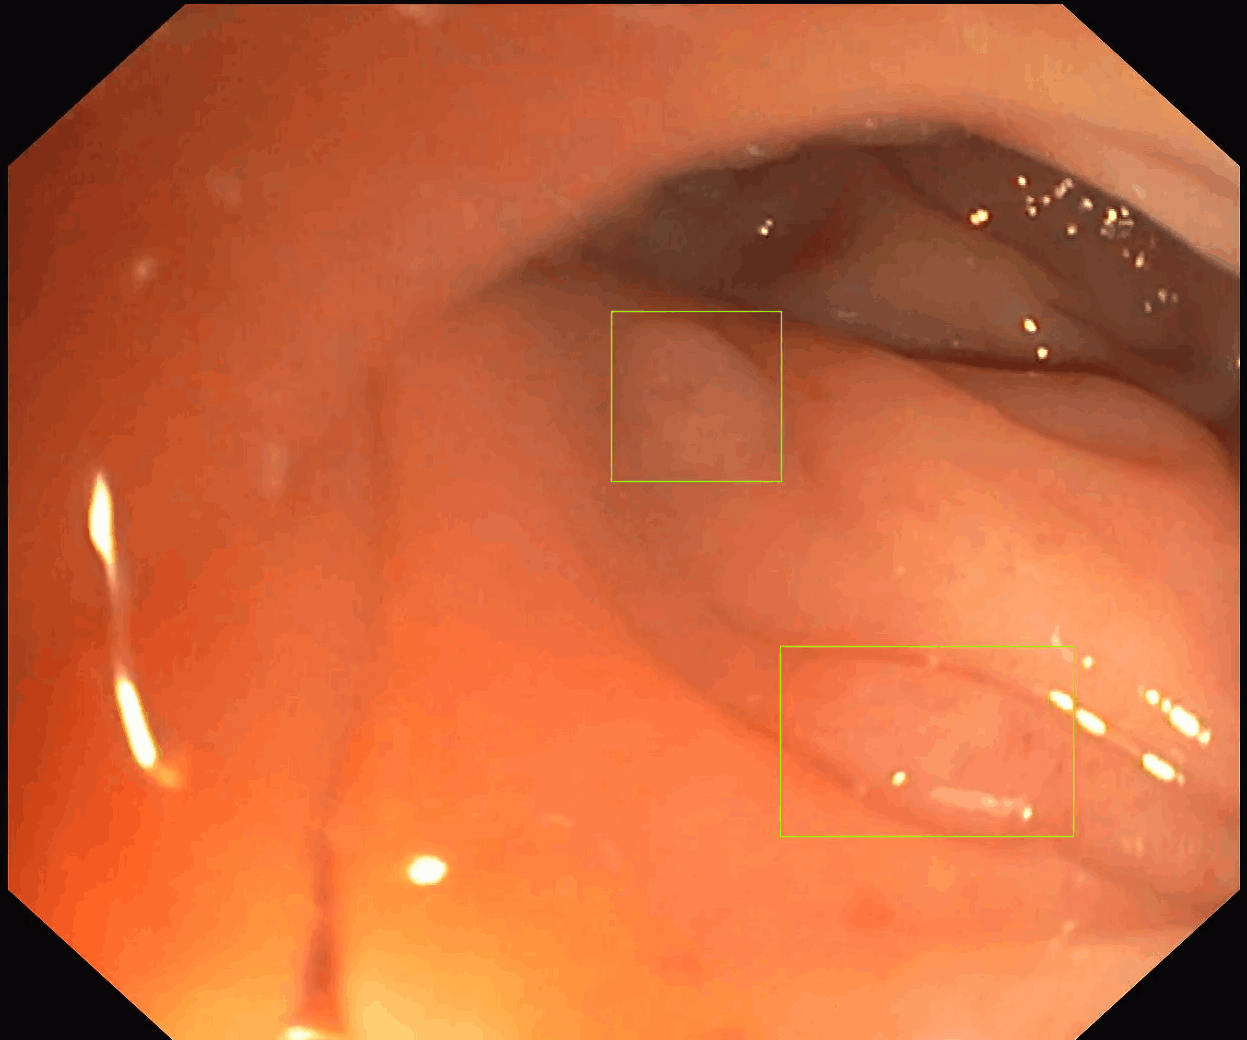

Our first product, SofiOne, is undergoing clinical validation as a decision support tool for the diagnosis of all polyp findings in colonoscopy.